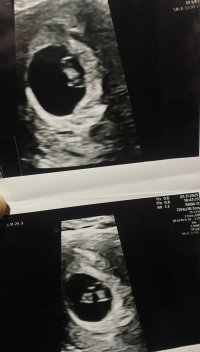

Fikk du høre hjertet når du var så kort på vei? Jeg fikk beskjed at de ikke ønsket å bruke doppler fordi det kunne forstyrre de når de var så små. Fikk bare sett hjertet slå. Jeg var 8+5.Vi hadde privat ultralyd 7+0 (mensdato 7+4), hvor vi hørte hjerteslag, så plommesekken, og lille ble målt til 8 mm og 7+5 (unøyaktig så tidlig sa hun)Vis vedlegget 474796Vis vedlegget 474797